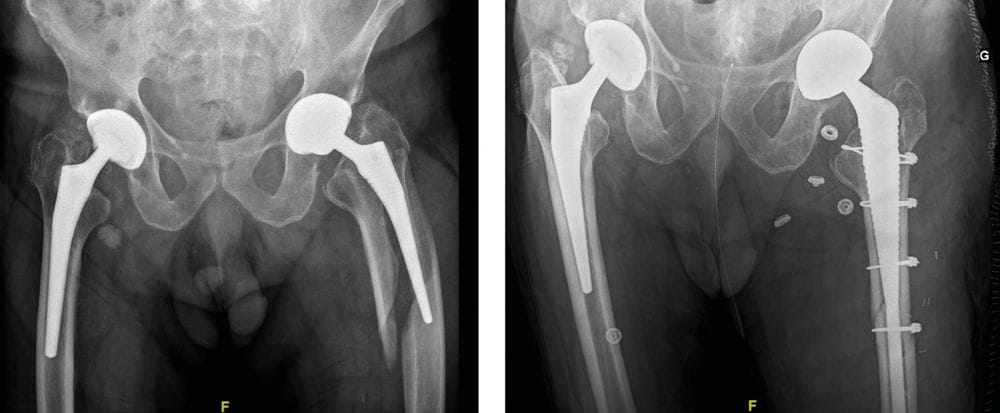

Examples of revision for periprosthetic fracture (PPF)

Case report n°1 (Figure 1)

- PPF at the cementless pivot (Vancouver B2)

- Two component revision: cementless monoblock long stem non-locking, fracture repair with cerclage wiring

- Dual mobility cup

Case report n°2 (Figure 2)

PPF at the cementless pivot (Vancouver B2) after acetabulum-only revision

Femur-only revision: cementless monoblock long stem Locking stem, fracture repair with cerclage wiring.